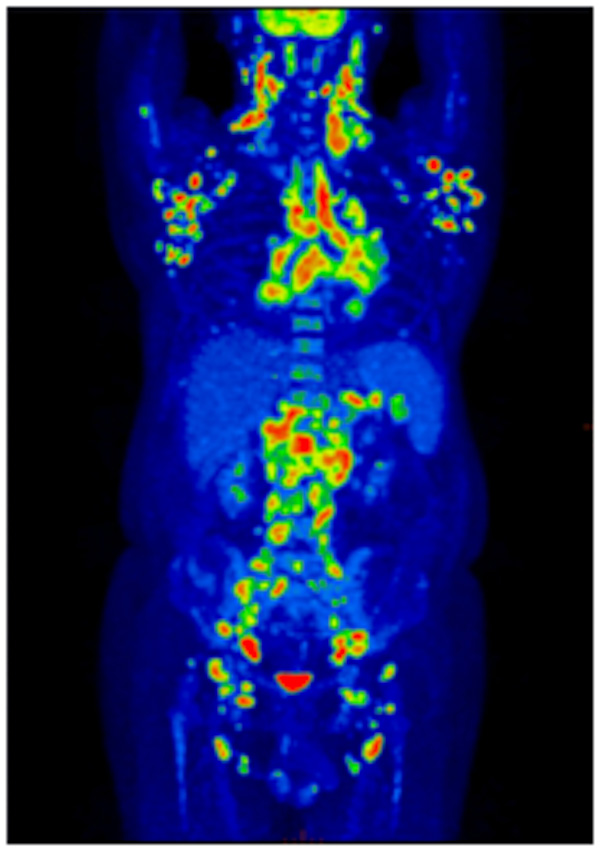

59歲黃先生因“發(fā)現(xiàn)右側(cè)頭枕部及雙側(cè)頸部腫物2月”在柳州市人民醫(yī)院血液內(nèi)科就診。入院查淺表器官超聲提示:雙側(cè)頸部及腋窩多個實質(zhì)性腫塊,考慮淋巴結(jié)腫大。經(jīng)過抗炎治療后右頸部淋巴結(jié)仍逐漸增大。實施右側(cè)頸部淋巴結(jié)切除活檢術(shù),術(shù)后病理提示:血管免疫母細(xì)胞性T細(xì)胞淋巴瘤。

患者頸部及腋窩的淋巴結(jié)是不是都是淋巴結(jié)浸潤?全身還有哪些地方受淋巴瘤的浸潤?為了進(jìn)一步得到準(zhǔn)確的結(jié)果,患者到核醫(yī)學(xué)科進(jìn)行PET-CT檢查,淋巴瘤病灶立即無所遁形!

▲患者全身MIP圖:全身多發(fā)淋巴結(jié)淋巴瘤浸潤(A)

PET-CT能夠一次獲得全身檢查圖像,除了頸部及腋窩,其他部位的病灶也能一覽無余,患者的臨床分期發(fā)生了改變,為臨床醫(yī)生選擇治療方案提供了極大的幫助。